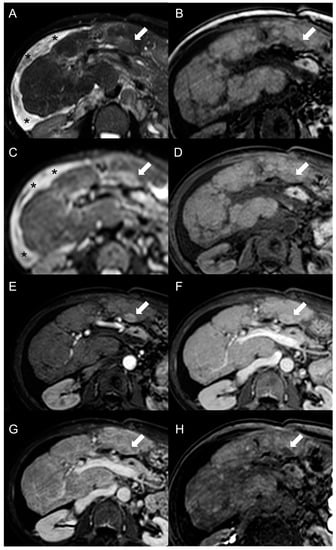

MRI features of FNH-like RNs are shown in Figure 3.

Figure 3.

MRI examination of a 29-year-old female with Budd–Chiari syndrome. On fat-saturated T2-weighted images (A) FNH-like RNs are barely discernable as they appear isointense to the liver parenchyma; occasionally, areas of very slightly hyperintense signal (arrow) can be identified, possibly related to congested nodules or central scar. On out-of-phase T1-weighted images (B) the presence of nodular lesions is more appreciable, as FNH-like RNs (arrow) appear slightly hyperintense compared to the surrounding liver parenchyma. On DWI (b-value = 600) (C), FNH-like RNs may show a slight heterogeneous hyperintensity due to central scar or congestion. On unenhanced gradient-echo T1-weighted images (D), the nodules (arrows) appear hyperintense, while on arterial phase (E) they show vivid enhancement with a peripheral hypointense rim due to hepatic tissue congestion. On portal venous (F) and delayed (G) phases, the nodules become progressively isointense to the liver. On the T1-weighted images (flip angle = 30°) in the hepatobiliary phase (H), FNH-like RNs show hyperintensity compared to the surrounding liver parenchyma.

However, considering that approximately 25% of HCCs do not display washout in the portal and delayed phases, while up to one-third of FNH-like RNs can show it, the specificity of this feature for the diagnosis of HCC in BCS is relatively low. As reported by Van Wettere et al. [22], the association of homogeneous APHE and homogeneous washout was identified in one-third of benign lesions and in half of HCC cases. The resulting sensitivity and specificity for diagnosing HCC were 50% and 70%, respectively. When considering the combination of any type of APHE (homogeneous, peripheral or central) and any type of washout (homogeneous or peripheral), a sensitivity of 100% and a specificity of 61% were achieved. For this reason, given the risk of an unacceptable rate of false-positive results, the LI-RADS and AASLD/EASL criteria for the non-invasive diagnosis of HCC cannot be applied in BCS patients [28,29,30]. The differential diagnosis between FNH-like RNs and HCC becomes even more challenging due to the potential for the former to increase in size and/or in number. Therefore, it is important to consider additional features supportive of diagnosis of HCC, such as T1 hypointensity, hyperintensity in T2-weighted and high b-value DWI, and absence of a central scar on MRI [42], as shown in Figure 6.

Figure 6.

MRI examination of a 67-year-old female patient with Budd–Chiari syndrome reveals a new focal lesion of 13 mm in the left lobe (arrow). The lesion appears hyperintense on T2-weighted images (A), hypointense on T1-weighted images (B,D) and shows restricted diffusion in high-b-value DWI (C). After contrast agent administration, the lesion demonstrates marked enhancement on T1-weighted arterial phase images (E), followed by central washout with enhancing capsule on T1-weighted portal venous (F) and delayed (G) phases. On T1-weighted images in the hepatobiliary phase (H) the lesion shows a hypointense signal, suggesting a diagnosis of HCC. Perihepatic ascites (asterisks) can be observed on T2-weighted images (A) and DWI (C).

Hepatobiliary contrast agents provide valuable help in the differential diagnosis, as HCC most often demonstrates a hypointense signal in HBP. In the above-mentioned study [22], the combination of this feature with APHE and washout proved effective in distinguishing all HCC lesions from FNH-like RNs. Indeed, benign regenerative lesions typically appear isointense-to-hyperintense compared to the normal liver in HBP, regardless of the presence of washout on portal venous or delayed phase images.

Hemangioma, true focal nodular hyperplasia, adenoma, dysplastic nodule, and necrotic regenerative nodule are other focal liver lesions that may coexist in patients with BCS (Figure 7).

Figure 7.

MRI examination of a 49-year-old female patient with Budd–Chiari syndrome reveals multiple lesions, including two large FNH-like RNs (arrows) in V-VI liver segment. On fat-saturated T2-weighted images (A), these nodules are iso-hypointense with an inhomogeneous central hyperintensity and a low-signal perinodular rim. On T1-weighted images (B) the FNH-like RNS appear hyperintense, one of them exhibiting a central hypointensity corresponding to the central scar. In DWI (b-value = 600) (C), they show the same signal intensity as the adjacent liver parenchyma, with appreciable low-signal peripheral rim. On T1-weighted unenhanced (D), arterial (E), portal (F), and delayed (G) phase images, the FNH-like RNs demonstrate inhomogeneous arterial enhancement and isointense signal on the portal and delayed phases; the hypointense perinodular rim, representing congested hepatic tissue, remains noticeable. In the hepatobiliary phase (H), the FNH-RNs display inhomogeneous iso-hyperintense signals compared to the surrounding liver parenchyma. A third lesion, compatible with a hemangioma (arrowhead), is also visible, showing homogeneous hyperintensity on fat-saturated T2-weighted images (A) and DWI (b-value = 600) (C), hypointensity on T1-weighted images (B), slow centripetal globular enhancement on arterial (E), portal (F), and delayed phase (G) images, and hypointense signals in the hepatobiliary phase (H).